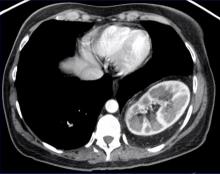

This video demonstrates a VATS repair in an adult of a recurrent, congenital Bochdalek hernia with intrathoracic herniation of the left kidney and a portion of the pancreas. A Bochdalek hernia is a congenital posterolateral defect of the diaphragm. It is more commonly seen in infants and predominantly occurs on the left side. Intrathoracic herniation of the stomach and intestine is also common. Incidence of associated intrathoracic kidney herniation is reported to be less than 0.25%. To the author’s knowledge, this is the first reported case of a VATS repair of this complex hernia.